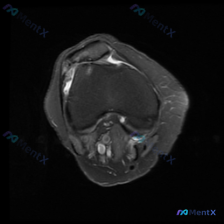

看到一份针对单张膝关节MRI的软骨异常评估咨询,整理了完整的分析思路分享给大家。 病例/影像基础信息 问题核心:用户提供单张膝关节轴位T1加权MRI图像,询问图像中是否存在软骨异常。 影像所见(基于提供图像): 1. 扫描层面为膝关节轴位,涵盖股骨远端滑车区与髌骨 2. 股骨髁、髌骨骨髓信号正常(T...